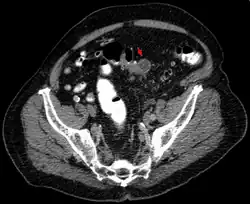

Sigmadivertikulitis in der axialen Computertomographie. Deutliche Wandverdickung und multiple Divertikel.

An Symptomen besteht ein plötzlich auftretender Schmerz über dem betroffenen Darmabschnitt am häufigsten im linken Unterbauch (deshalb auch Linksseiten-Appendizitis) oft mit Ausstrahlung in den Rücken und mit einer auf diesen Bereich begrenzten Peritonitis. Daneben sind häufige Symptome Fieber, Übelkeit, Erbrechen, eine Veränderung des Stuhlverhaltens von Durchfall bis Verstopfung mit Eiter und Schleim im Stuhl und Schwierigkeiten beim Wasserlassen, Dysurie genannt. In den Laborwerten fallen eine Erhöhung des CRPs und der Leukozyten auf. Teilweise kann bei der Untersuchung des Bauches des Betroffenen ein walzenförmiger Tumor (Tumor im Sinne einer raumfordernden Geschwulst) getastet werden. Die weitere Diagnostik erfolgt u. a. mit dem Ultraschall und einer CT-Untersuchung des Bauches. Bei der akuten Divertikulitis wird die Durchführung einer Darmspiegelung wegen des Risikos einer Perforation vermieden. Darmspiegelungen werden lediglich in Intervallen durchgeführt, um andere – insbesondere bösartige – Erkrankungen auszuschließen.[8]